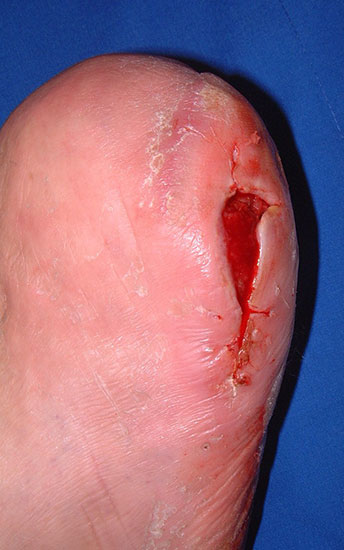

Nekrose an der Großzehe (Abb. 2)

Eitrig-infiziertes Ulkus an der Spitze der 2. Zehe als Indikation zur Endgliedamputation.

Chronisches Ulkus mit Infektion (Abb. 13).